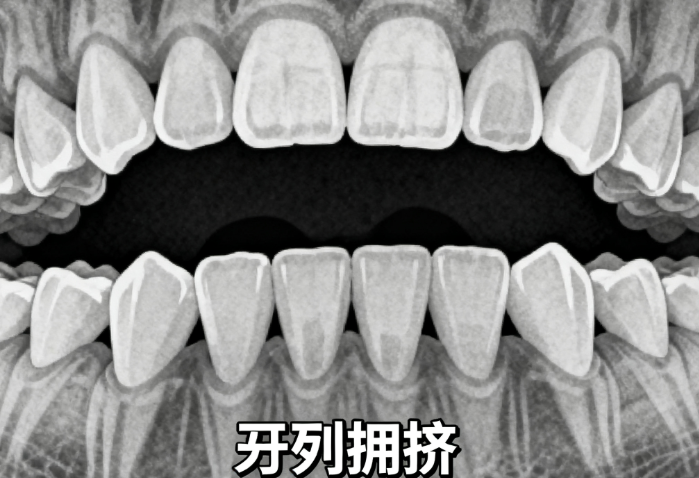

时代天使作为国产隐形矫正代表,用高颜值牙套+3D定制技术火了。磨砂材质戴起来像隐形眼镜,比国外品牌更贴合亚洲人牙型。价格比进口便宜20%,戴半年就能让牙齿排整齐。现在连小孩戴也